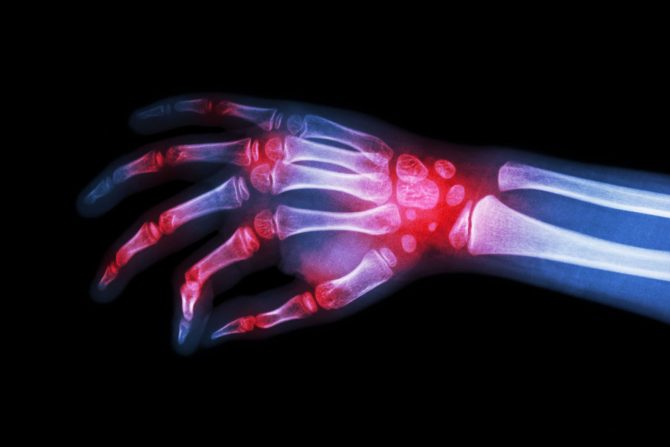

Reumatoidni artritis je hronična autoimuna bolest koja nastaje kada imuni sistem čoveka počne da napada tkivo koje oblaže zglobove. Tačan uzrok bolesti još uvek je nepoznat a opcije lečenja podrazumevaju  promenu načina života, fizikalnu terapiju, radnu terapiju, terapiju ishranom, lekove i operaciju. Ono što reumatoidni artritis čini drugačijim od drugih vrsta artritisa je što se  javlja u zglobovima, na obe strane tela, ali i činjenica da može da izazove razvoj i nekoliko drugih oboljenja.

Simptomi reumatoidnog artritisa (RA) najčešće su bol i upale u prstima, šakama/rukama, zglobovima, kolenima, gležnjevima, stopalima i prstima na nogama. Nekontrolisana upala oštećuje hrskavicu, koja obično deluje kao „amortizer” u zglobovima. Vremenom, to oštećenje može da deformiše zglobove i na kraju sama kost erodira. Ovo stanje može da dovede do fuzije zgloba, promene koja otežava telu da se zaštiti od stalne iritacije. Specifične ćelije u imunološkom sistemu pomažu u ovom procesu i te supstance, koje se proizvode u zglobovima, cirkulišu i izazivaju simptome po celom telu. Pored toga što utiče na zglobove, reumatoidni artritis ponekad utiče na druge delove  tela, kao što su: